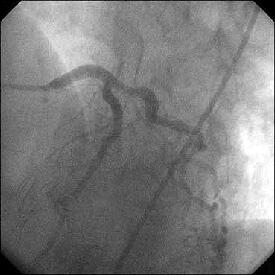

�Ǘ��72�Ώ����Brisk factor��HT, HL, DM�ł��B

��2�T�ԑO�̔��ǂƎv����Recent MI�ł��BLAD#7: total��Tristar3.0�~18?�����

�܂����B

����LCx ostium: 75%�ł��B������PCI���悤�Ǝv���̂ł����A�ǂ̂悤��strategy

���l������ł��傤���H

���Ȃ݂ɓ��@�ł�DCA�g�p�o���҂͂��܂���B

DCA�ł���l��A��Ă���A�Ƃ����I�������܂߂Č䏕��������K���ł��B

�X�������肢���܂��B

|

|

|

|

|

����������������������������������������������������������������������������